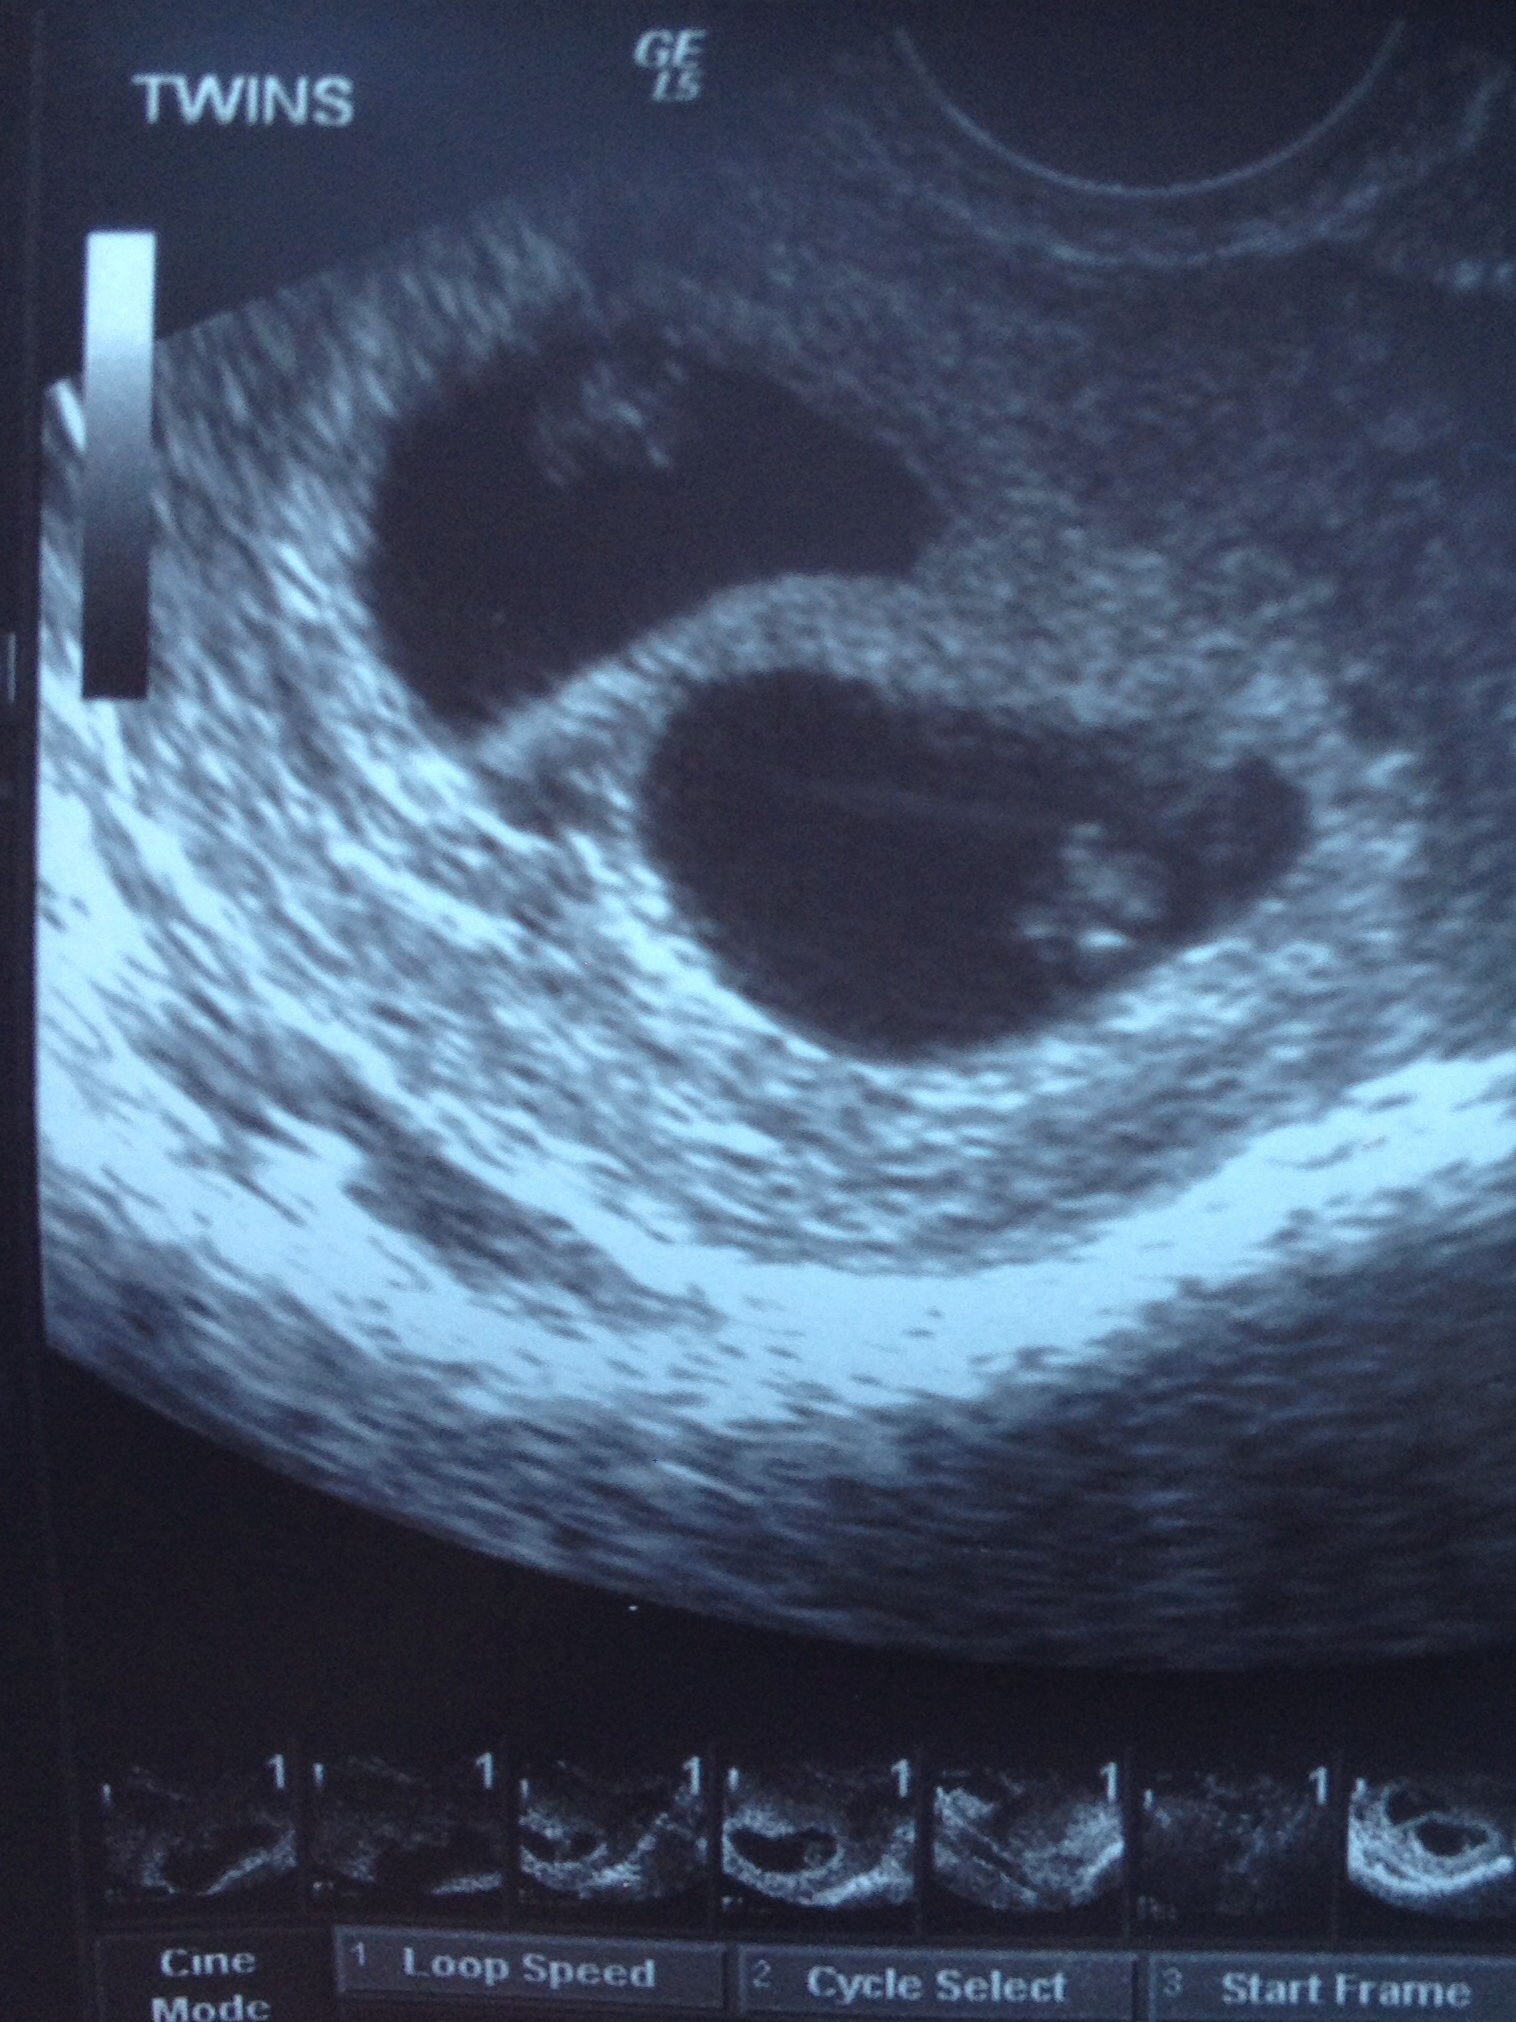

We're having twins!!!!! Got to see our little ones and their perfect little heartbeats for the very first time this morning. Measuring right on track. 6w5d--EDD 05/14/2014